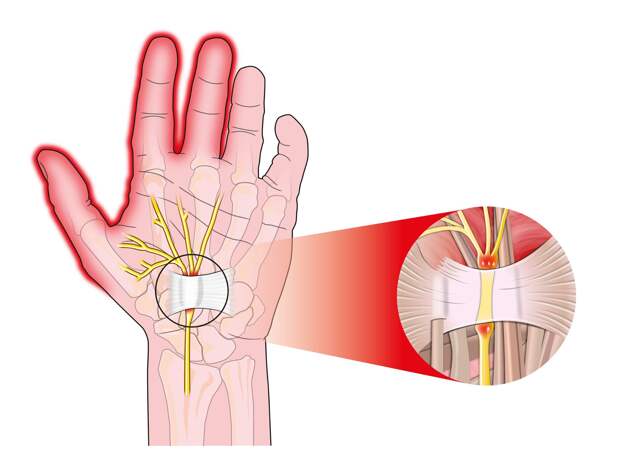

В действительности эти симптомы могут указывать на сдавление в запястном (карпальном) канале срединного нерва. Это состояние часто называют туннельным синдромом. Вообще, это целая группа заболеваний, связанных с защемлением нервов и сосудистых пучков в туннелях или каналах, которые образуются мышцами, костями и сухожилиями. Запястный туннельный синдром считается одним из наиболее частых.

Это состояние может быть обусловлено травматизацией или компрессией. При травме туннельный синдром возникает из-за отека мышц и связок, что приводит к сдавливанию нерва и нарушению его функции. Из-за пережима нерва возникает ощущение онемения и покалывания.

На начальной стадии проявление симптомов может быть малозаметным. Например, мурашки (парестезии) могут проявляться по утрам и проходить в течение пары часов. Чувство онемения и боль в начале заболевания могут носить легкий характер и проходить при смене позы, потряхивании рукой, опускании кисти вниз.

Пускать туннельный синдром на самотек медики не советуют. При отсутствии лечения состояние будет неминуемо прогрессировать. Если туннельный синдром не лечить, рука будет терять силу, начнет пропадать ловкость в движениях, снизится чувствительность. Также может развиться атрофия мышц.

Как правило, туннельный синдром диагностируется при комплексном обследовании, в которое могут входить анализы крови, в частности, на ревматоидный фактор, С-реактивный белок, антистрептолизин-О, УЗИ, МРТ, электронейромиография.